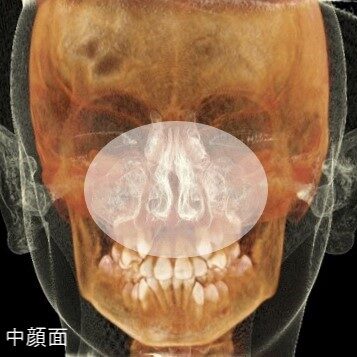

気道容積と鼻副鼻腔容積の変化イメージ

受け口そのものとは離れますが、無関係なお話しではありません。ランパセラピーでは「中顔面の骨格的な発達不良」を歯並びが悪くなる主な原因と捉えています。

もう一点、舌が上顎につかないことによって、中顔面(上顎)には支えがなくなり、重力の影響によって下方へ成長します。対抗する力はありません。すると顎骨には歪みが生じ、鼻腔の狭小化へと繋がります。さらに下がった上顎に連動して、下顎も後下方へ回転するように下がります。これらの動きは、気道を物理的に圧迫します。

つまり、中顔面の下方成長は、鼻腔と気道を物理的に狭くさせ、口呼吸しかできない状態にします。「息苦しい」を感知した脳は、少しでも気道を拡げようと、下顎を前に出したり、頭ごと前に出したりして対応します。酸欠の身体の緊急措置です。ここにも出てきますね、受け口。

上顎にきちんとついた舌は、黄矢印②の中顔面の下方成長、そして黄矢印③の唇側からかかる力とのバランスを取り、中顔面の正しい成長と歯並びの形成において重要な役割を担っています。

RAMPAの装置とご家庭の努力で、中顔面(上顎)の位置を上げ、骨格を可能な限り正しい形に戻してあげる。そうすれば、鼻副鼻腔は拡がり、気道の圧迫も解放されます。そうすれば、鼻呼吸ができる環境と歯が並ぶ環境が整います。

中顔面の発達不良